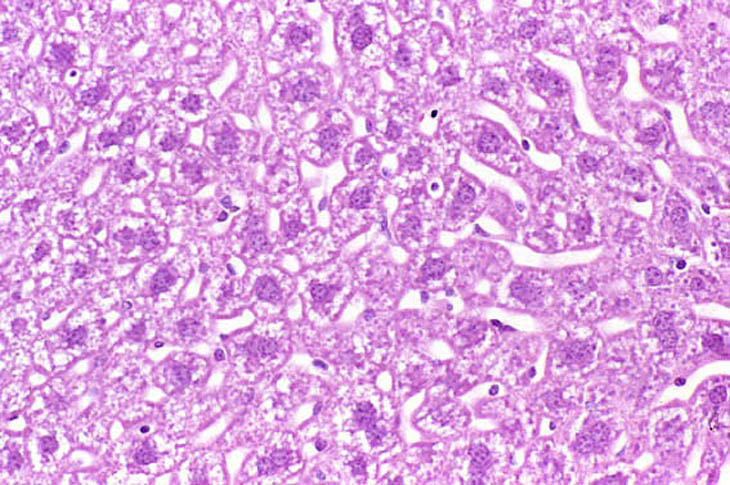

Perfusion fixation of the liver from a non-fasted mouse. Fixative was 10% NBF.